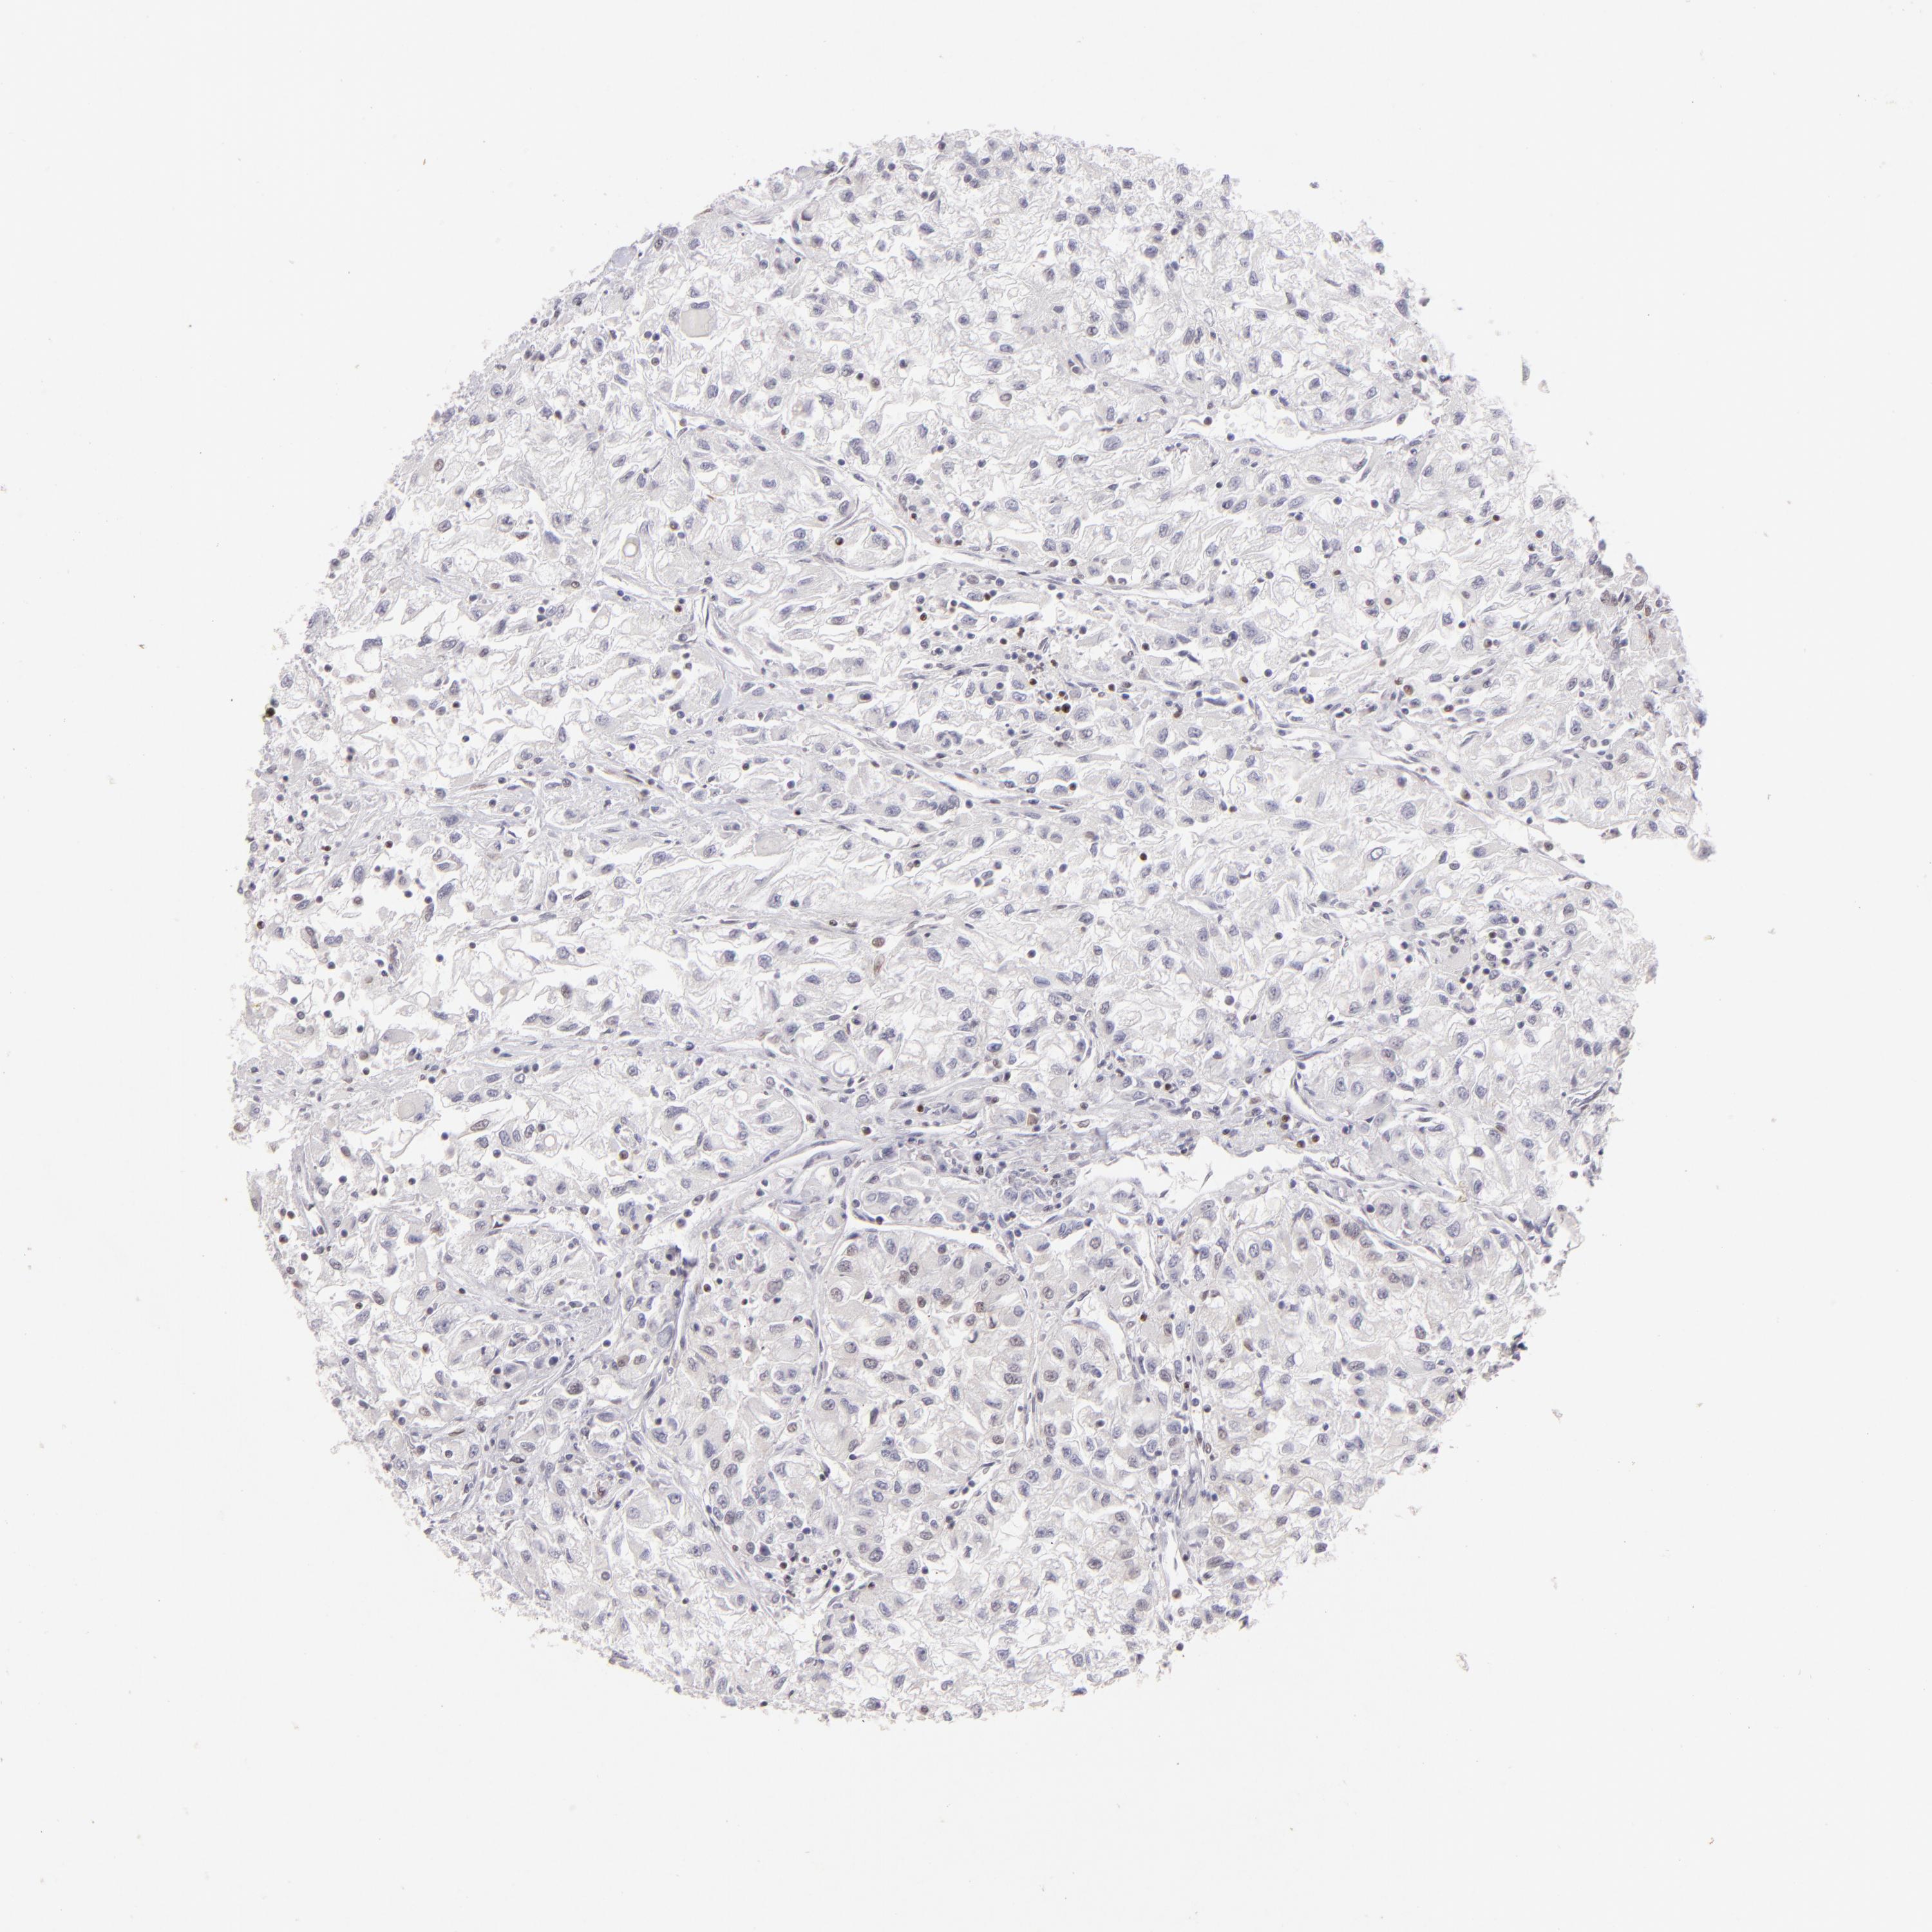

KIDNEY RENAL CLEAR CELL CARCINOMA (VALIDATION) - Interactive survival scatter ploti

The Survival Scatter plot shows the clinical status (i.e. dead or alive) for all individuals in the patient cohort, based on the same data that underlies the corresponding Kaplan-Meier plots. Patients that are alive at last time for follow-up are shown in blue and patients who have died during the study are shown in red.

The x-axis shows the expression levels (FPKM) of the investigated gene in the tumor tissue at the time of diagnosis. The y-axis shows the follow-up time after diagnosis (years). Both axes are complimented with kernel density curves demonstrating the data density over the axes. The top density plot shows the expression levels (FPKM) distribution among dead (red) and alive patients (blue). The right density plot shows the data density of the survived years of dead patients with high and low expression levels respectively, stratified using the cutoff indicated by the vertical dashed line through the Survival Scatter plot. This cutoff is automatically defined based on the FPKM cutoff that minimizes the p-score. The cutoff can be changed by dragging the vertical line or by entering a cutoff value in the square labeled "Current cut-off".

Under the Survival Scatter plot the p-score landscape (black curve; left axis) is shown together with dead median separation (red curve; right axis). Dead median separation is the difference in median mRNA expression between patients who have died with high and low expression, respectively. It is calculated as follows: median FPKM expression of dead patients with high expression - median FPKM expression of dead patients with low expression. This is intended to aid the user in visually exploring custom cutoffs and the associated p-scores and dead median separation.

Individual patient data is displayed and can be filtered by clicking on one or more of the category buttons on the top of the page. Categories describing expression level and patient information include: high, low, alive, dead, female, male and tumor stages. The scale of the x-axis can be toggled between linear and log-scale by clicking on the "x log" button. Mouse-over function shows TCGA ID, patient information and mRNA expression (FPKM) for each patient.

& Survival analysisi

Kaplan-Meier plots summarize results from analysis of correlation between mRNA expression level and patient survival. Patients were divided based on level of expression into one of the two groups "low" (under cut off) or "high" (over cut off). X-axis shows time for survival (years) and y-axis shows the probability of survival, where 1.0 corresponds to 100 percent.

POU2F1 is not prognostic in Kidney Renal Clear Cell Carcinoma (validation)

: 3.37

Average pTPM 3.2

Number of samples 100